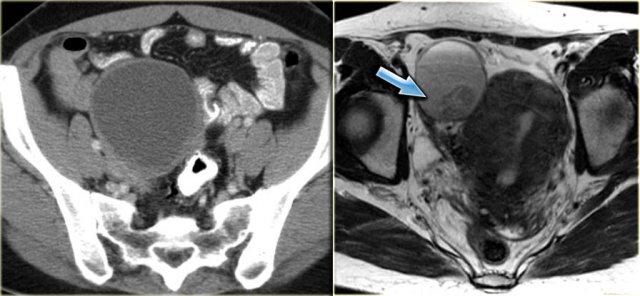

Trường hợp tiếp theo là siêu âm qua thành bụng cho thấy một khối nang đa thùy bên trái.

Hình ảnh này gợi ý u nang tân sinh buồng trứng nhưng không xác định được buồng trứng.

CT trên cùng bệnh nhân cho thấy một khối nang đa thùy tiếp giáp bàng quang, có liên quan đến tĩnh mạch buồng trứng trái (mũi tên).

Có các vách ngăn dày và thành dày không đều.

Dựa trên hình ảnh CT này, không thể phân biệt giữa tổn thương buồng trứng lành tính như u nang tuyến xơ và tổn thương buồng trứng ác tính.

Tổn thương được phẫu thuật cắt bỏ và kết quả giải phẫu bệnh xác định là u nang tuyến xơ.